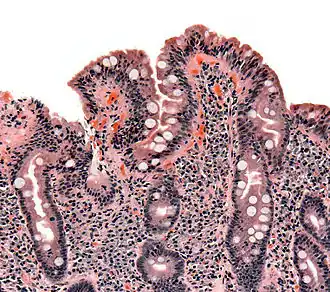

- Etapa a doua – în care diagnosticul este pus de medicul specialist pediatru, gasto-enterolog sau dermatolog, la care se fac analize specializate de anticorpi specifici celiachiei, care se certifică printr-o biopsie de jejun. Aceasta arată mucoasa digestivă deteriorată.